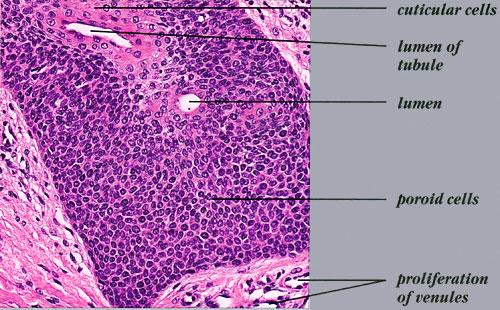

The term poroma refers to a group of rare cutaneous appendage tumors composed of cells (cuticular and poroid cells) similar to those of the acrosyringium. Poromas are traditionally subcategorized histopathologically based on their location in relation to the epidermis into three main variants; namely, hidroacanthoma simplex, eccrine poroma, and dermal duct tumor. Some authors add poroid hidradenoma to this group. There are also reports of “poromas” with differentiation toward the folliculosebaceous-apocrine unit.

Hidroacanthoma simplex shows sharply demarcated aggregations of cuboid to ovoid cells confined to the epidermis. Eccrine poroma reveals aggregations of uniform basaloid cells that radiate from the basal layer of the epidermis into the dermis . Dermal duct tumor consists of several sharply circumscribed, mainly dermal nodules composed of poroid and cuticular cells. Ductal structures are frequently observed. Poroid hidradenoma is characterized by intradermal, solid, and cystic aggregations of poroid cells.